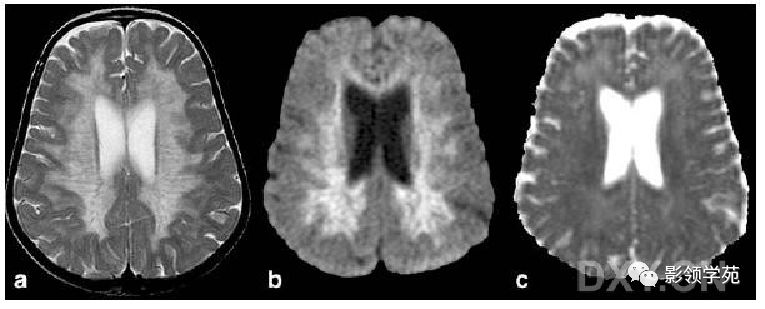

病因: 脂肪代谢紊乱所致,患者体内缺乏乙酰辅酶A合成酶,不能将特长链脂肪酸切断,使之在组织中、尤其在脑和肾上腺皮质沉积,导致脑白质和肾上腺皮质破坏。多为3岁~12岁儿童。 病灶呈T1加权低信号、T2加权像高信号改变,常经胼胝体压部连接两侧三角区病灶,呈现“蝶翼”样形状。 晚期大脑白质普遍出现异常改变、无强化时,仅凭影像学表现很难与其它脱髓鞘疾病鉴别。